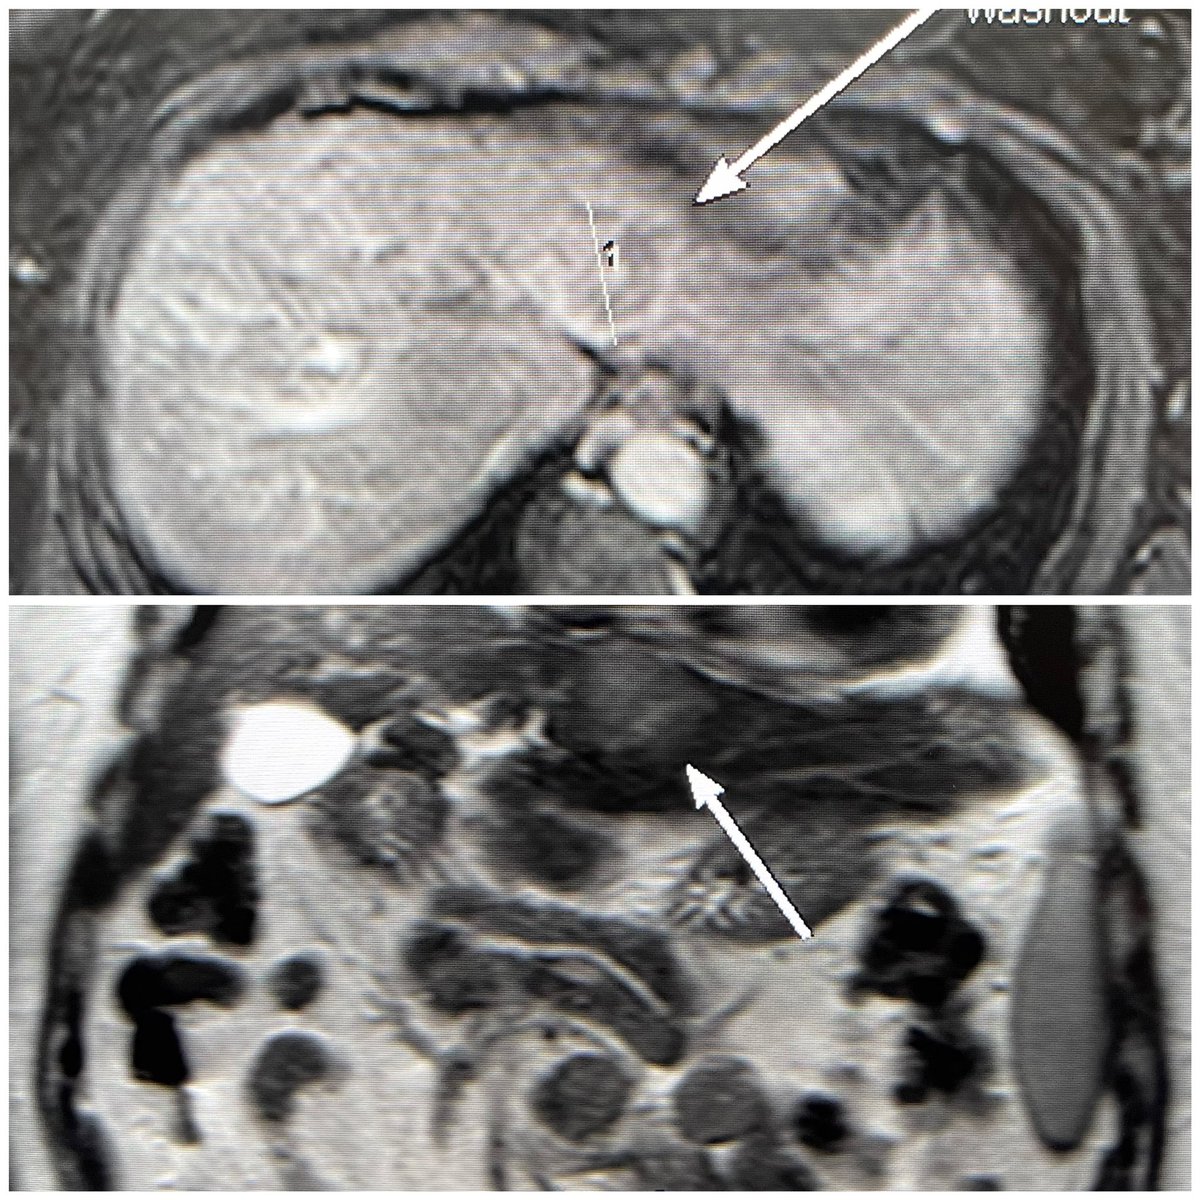

Left lateral hepatic lobe HCC supplied by two & three segmental arteries treated with high dose Y90. Fusion images show complete coverage of the tumor & SPECT CT targeted tumor dose #personalized #dosimetry #y90 #radioembolization @UTHouston_IR @UTHradiology @memorialhermann

1

3

25